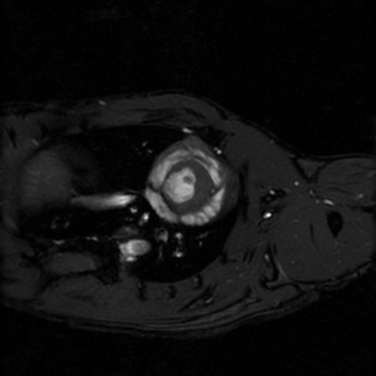

• Kardiyak görüntüleme

Kısa eksen, uzun eksen ve dört odacık kardiyak görüntüler prospektif tetikleme ile veya retrospektif olarak elde edilebilir.